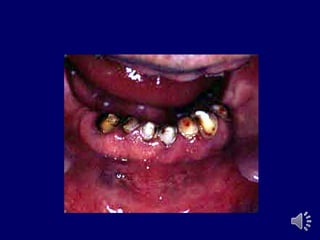

Overdenture Risks

butment

aries

ear

eriodontium

ingivitis

eriodontitis